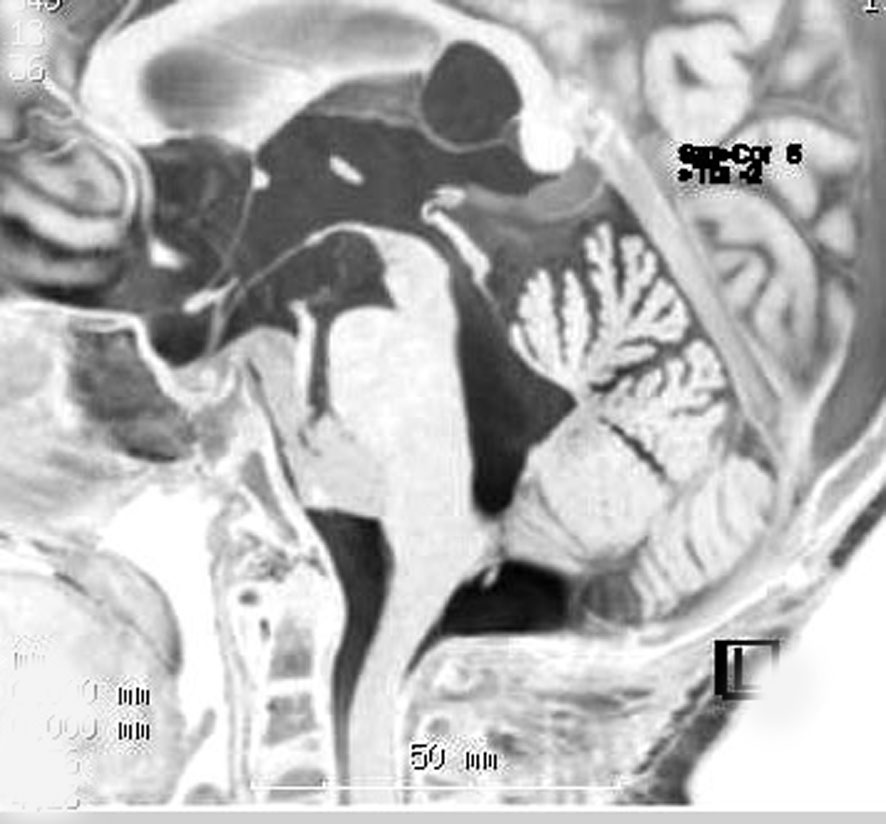

幼児の巨大な上衣腫です。左ルシュカ孔から延髄を取り囲む様に小脳延髄角槽に進展しています。最も典型的で治療が難しいタイプです。これはT2強調画像ですが,ガドリニウム増強されないものでした。

左が術前,右が術後です。脳底動脈の周囲が摘出できませんでした。幼児ですが手術後には局所照射をするしか方法がありません。